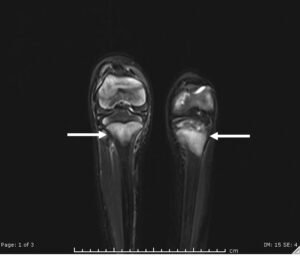

Scurvy. MRI T2-weight STIR sequence. JETem 2021